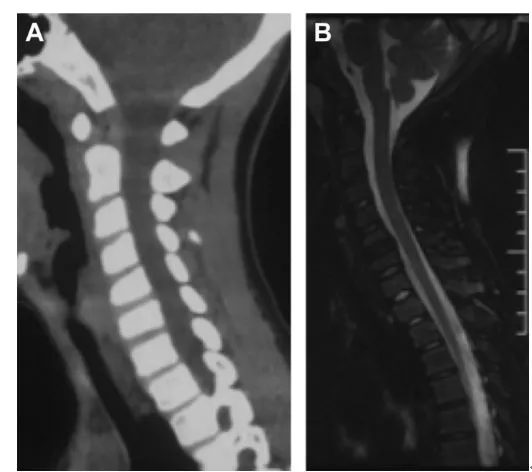

明確診斷主要透過影像學方法,頸椎CT是關鍵。頸長肌鈣化性肌腱炎特異性的影像表現是C1-4椎體前緣軟組織腫脹和積液與C1椎體前弓下方不規則鈣化沉著共存。

圖:C1椎體前弓下方不規則鈣化沉著

圖:椎前積液

圖:椎前積液和C1椎體前弓下方不規則鈣化沉著

圖:椎前軟組織腫脹

頸椎側位片能夠顯示上頸椎前縱韌帶和頸長肌組成的軟組織影增寬,密度增高,正常時寬度為3-4mm,急性炎性水腫時可增寬到1cm以上,並可顯示椎前軟組織內的鈣化影,一般位於C1-2水平。此外,還可見頸肌痙攣引起的頸椎前凸消失。頸椎側位平片所見的發育性寰椎前弓的下方附屬小骨片、寰椎前弓的撕脫骨折以及莖突舌骨肌韌帶的鈣化極易與本病所見的鈣化混淆。

CT的高解析度能夠明確肌腱內的鈣化,能夠明確是鈣化而不是其他骨骼來源的高密度影。鈣化一般位於寰椎前弓的下方和樞椎齒狀突的前方,少部分可位於下頸椎前側。CT有助於明確椎體前積液的存在和排除其他病理表現,如骨折或膿腫。MRI對診斷不是必須,但有時可幫助確定軟組織異常,排除咽後膿腫,脊椎炎或腫瘤。MRI檢查T2加權在椎前可見侷限性的裂隙樣區域,大多位於C1-4水平,呈高訊號改變,這反應是由於炎症引起的積液。T2加權、脂肪抑制序列和T1加權對鑑別積液和脂肪組織、含脂肪的骨髓以及咽後感染、脊椎炎有重要作用。MRI檢查在鈣化檢查方面存在不足,T2加權呈低訊號。

典型病例介紹

36歲女性,急性頸痛、吞嚥困難伴頸部僵硬,MRI示C1-2前部頸長肌增厚呈低訊號,提示鈣化(長箭頭)和C1-4椎前積液(無線箭頭),經類固醇和止痛藥治療8天后症狀消失,複查MRI提示上述表現消失。(PMID: 18765656)

C1-2前側低訊號(無線箭頭)和C1-5椎前水腫(長箭頭) (PMID: 19567634)